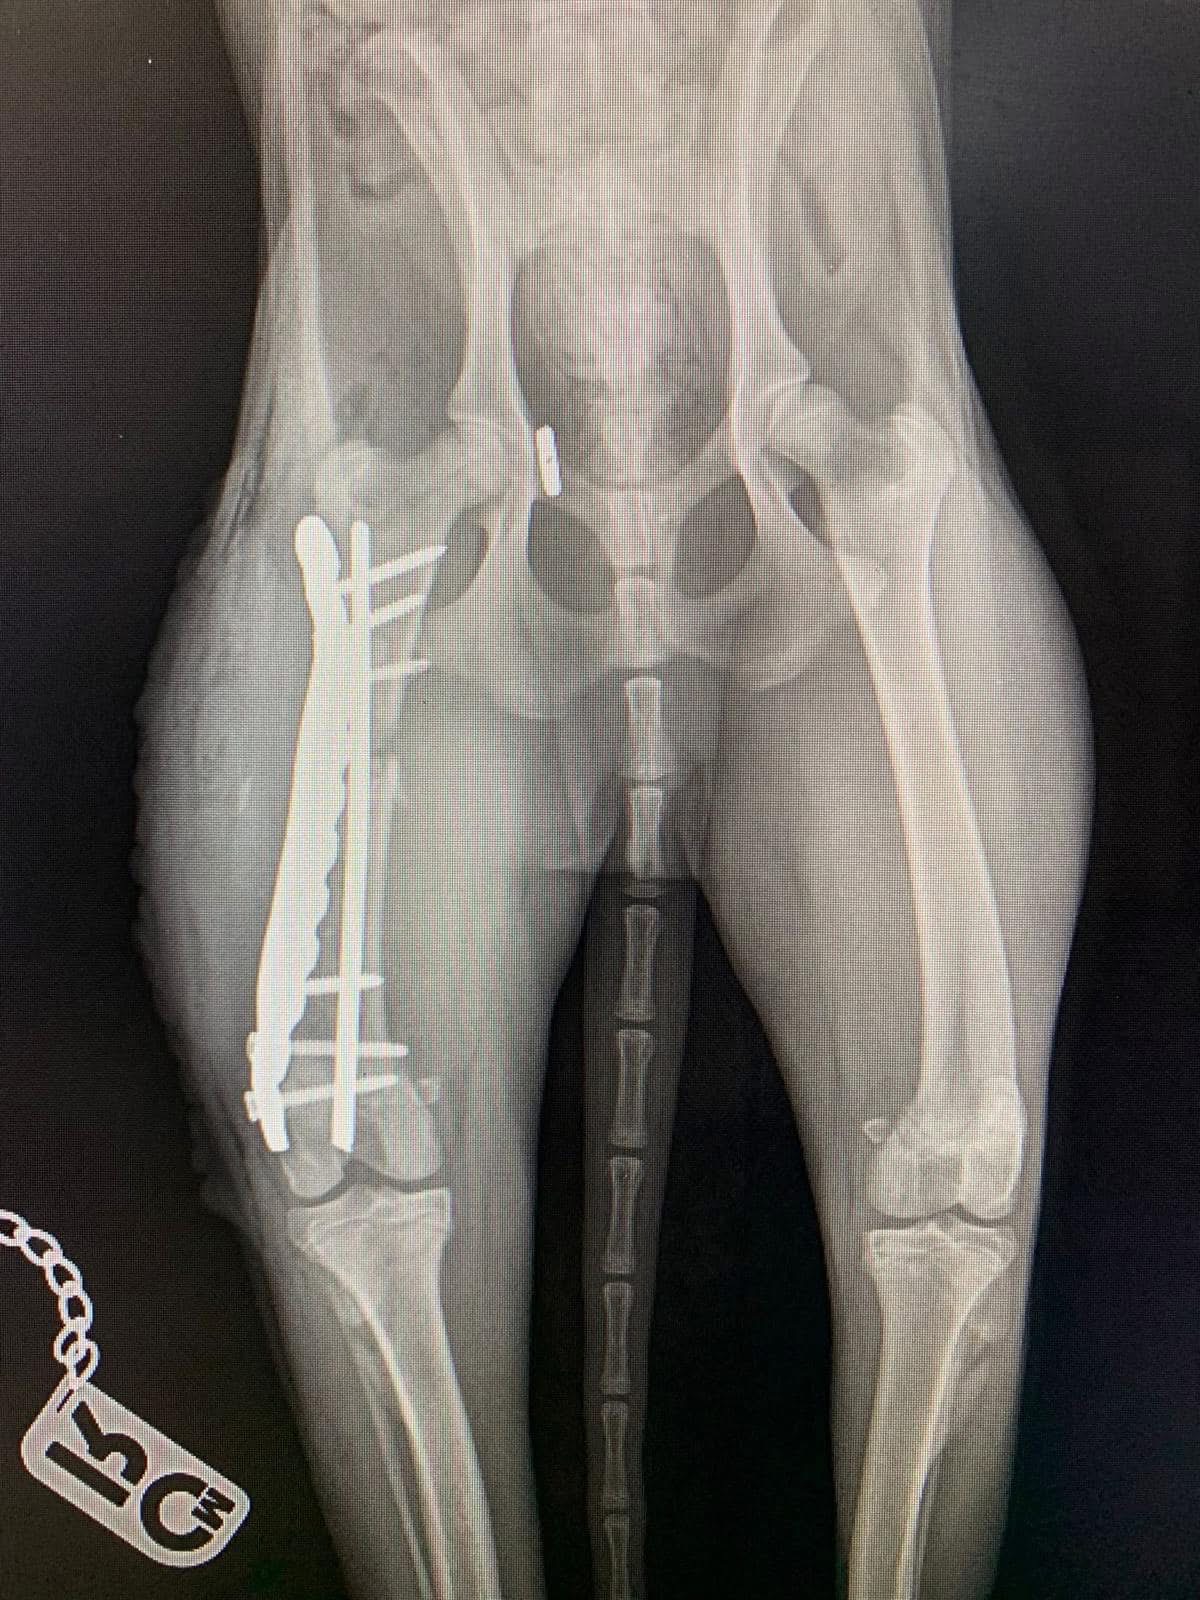

- Liječenje prijeloma kostiju, uključujući intraartikularne frakture

- Liječenje luksacije patele(Luxatio Patellae) Trohleoplastika i TTT(eng. Tibial Tuberosity Transposition)

- Korektivne osteotomije za ispravljanje deformiteta

- Liječenje rupture prednjeg križnog ligamenta koljena TPLO (eng. Tibial Plateau Leveling Osteotomy)